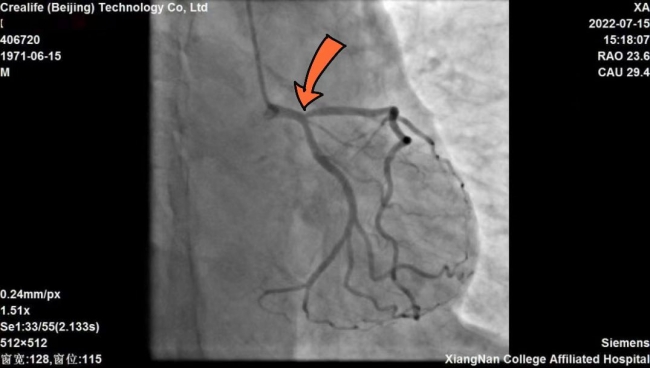

51岁的患者邓某,因反复活动时胸闷胸痛半月有余,遂入湘南学院附属医院心血管内科求诊治疗。接诊后,经心电图和冠脉造影检查显示:邓某左前降支开口70%狭窄,为临界病变,被诊断为冠心病、不稳定型心绞痛。按照传统治疗观念,邓某可能需要植入冠脉支架以改善心肌缺血。

▲患者冠脉造影显示箭头所指位置为病变处